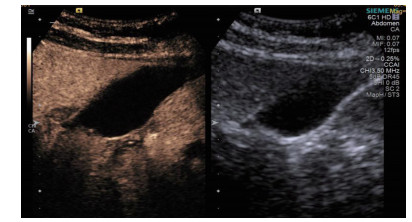

1.3 手术过程 1.3.1术前经肘静脉超声造影:行PTGBD前半h经肘静脉快速团注SonoVuel 5 mL,在对比脉冲序列造影成像模式下进行观察,根据不同组织造影剂凝聚的时间及浓度差异,判断胆囊周围组织黏连程度、胆囊壁完整程度(图 1),如出现胆囊壁造影剂充盈缺损(图 2、3),则考虑胆囊壁坏死或穿孔,根据静脉造影情况选择合适的置管入路,避开胆囊穿孔的部位及黏连组织。

| 图 2 穿刺后经引流管超声造影,显示置管路径(箭头处) |

术后再次经肘静脉超声造影同时经引流管超声造影:PTGBD后,再次经肘静脉快速团注SonoVuel 2 mL,在造影成像模式下进行观察肝脏被膜、胆囊床穿刺路径有无造影剂外渗,腹腔内有无外渗凝聚的造影剂,判断有无活动性出血及出血程度,如判断出血速度快、出血量较大,考虑动脉性出血,及时改为开腹或腔镜手术止血。PTGBD术后经引流管超声造影,置管成功后快速抽出胆囊内残留胆汁,减轻胆囊压力后,在超声造影模式下直接经引流管注入配制待用的稀释声诺维造影剂20 mL,实时动态的观察造影剂在胆囊腔内的充盈范围(图 2、3),评估引流管的通畅程度及引流范围、观察其在胆囊腔内的位置走形及卷曲情况、观察胆囊周边及腹腔内有无造影剂外渗。如患者腹痛症状加剧,结合经引流管超声造影判断有胆汁漏出表现,应持续监测观察患者生命体征及保守治疗效果,必要时及时改行开腹或腔镜手术治疗。